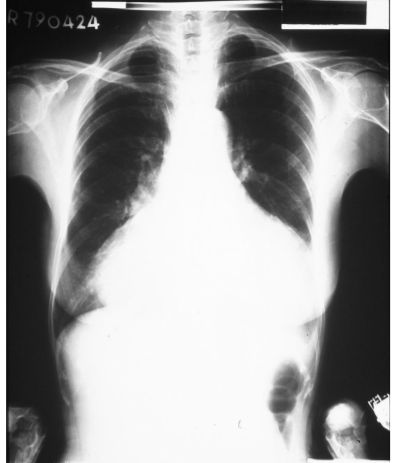

2. 37歲女性主訴進行性呼吸困難、倦怠、便秘但無發燒,身體檢查臉部浮腫、貧血,BP 126/94 mmHg、PR 104/min,胸部X光如圖,最可能的診斷是: (A) 肥胖併代謝症候群 (B) 黏液水腫性心臟病變 (C) 結核性心包膜炎 (D) 充血性心衰竭 (E) 高血壓心臟病